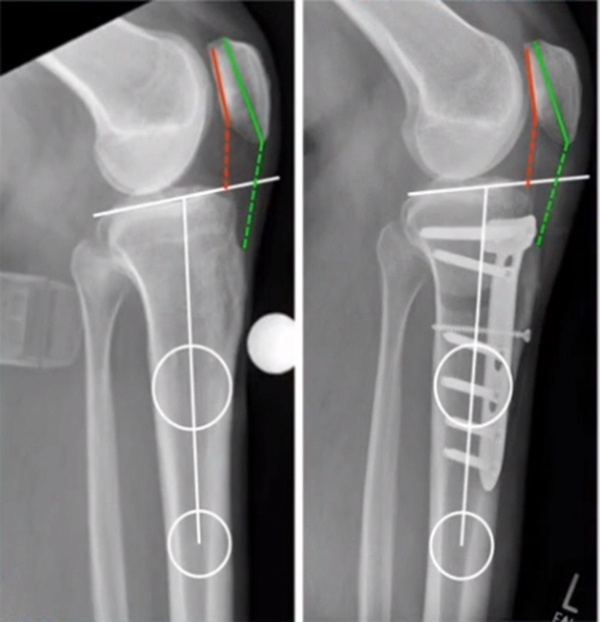

4OWHTO对髌骨高度影响?

1OWHTO可分为上行性或下行性两种截骨方式。

2)上行性OWHTO可降低髌骨高度的2%-11%;当髌骨高度下降10%,可引起髌股关节压力改变,引发膝前痛。

OWHTO上行截骨与下行截骨

3)下行性OWHTO对髌骨高度影响较小。

4)术前存在低位髌骨、髌股关节炎或内翻矫正度数较大时可考虑下行性OWHTO

有文献证实下行截骨对髌骨的高度确实没有明显影响。

OWHTO下行截骨对髌骨的影响

典型病例,男性,65岁,农民,双膝内翻16度。

术前影像

第一次为该患者做了传统上行开放截骨,撑开角度较大,术后用三种方法测量髌骨高度,发现髌骨高度受到影响,髌骨变低了。

左膝上行OWHTO(初次)

上行OWHTO髌骨高度测量

ISI法测量髌骨无明显变化;CDIBPI法测量髌骨降低明显;患者屈膝锻炼困难。

第二次来院做另一侧肢体时,采用下行截骨,术后患者髌骨高度,无论用哪种方法测量都无明显变化,而且患者膝关节功能迅速得到恢复。

右膝下行OWHTO(再次)

下行OWHTO髌骨高度测量

ISI法测量髌骨无明显变化;CDIBPI法测量髌骨无明显变化;患者屈膝明显改善。